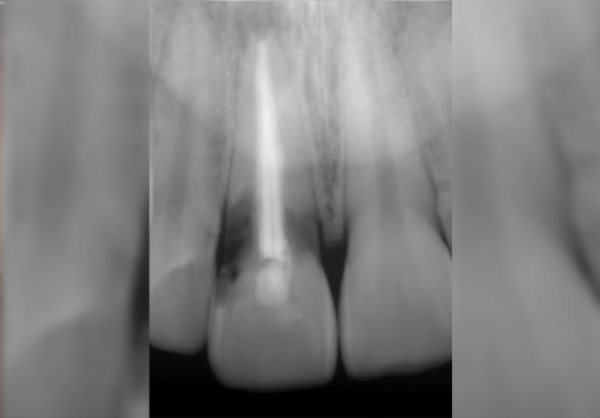

Cas du Docteur Maxime Collangettes

Esthétique, mise en charge immédiate et implant de petit diamètre

pour remplacer une agénésie d incisive latérale maxillaire, chirurgie guidée